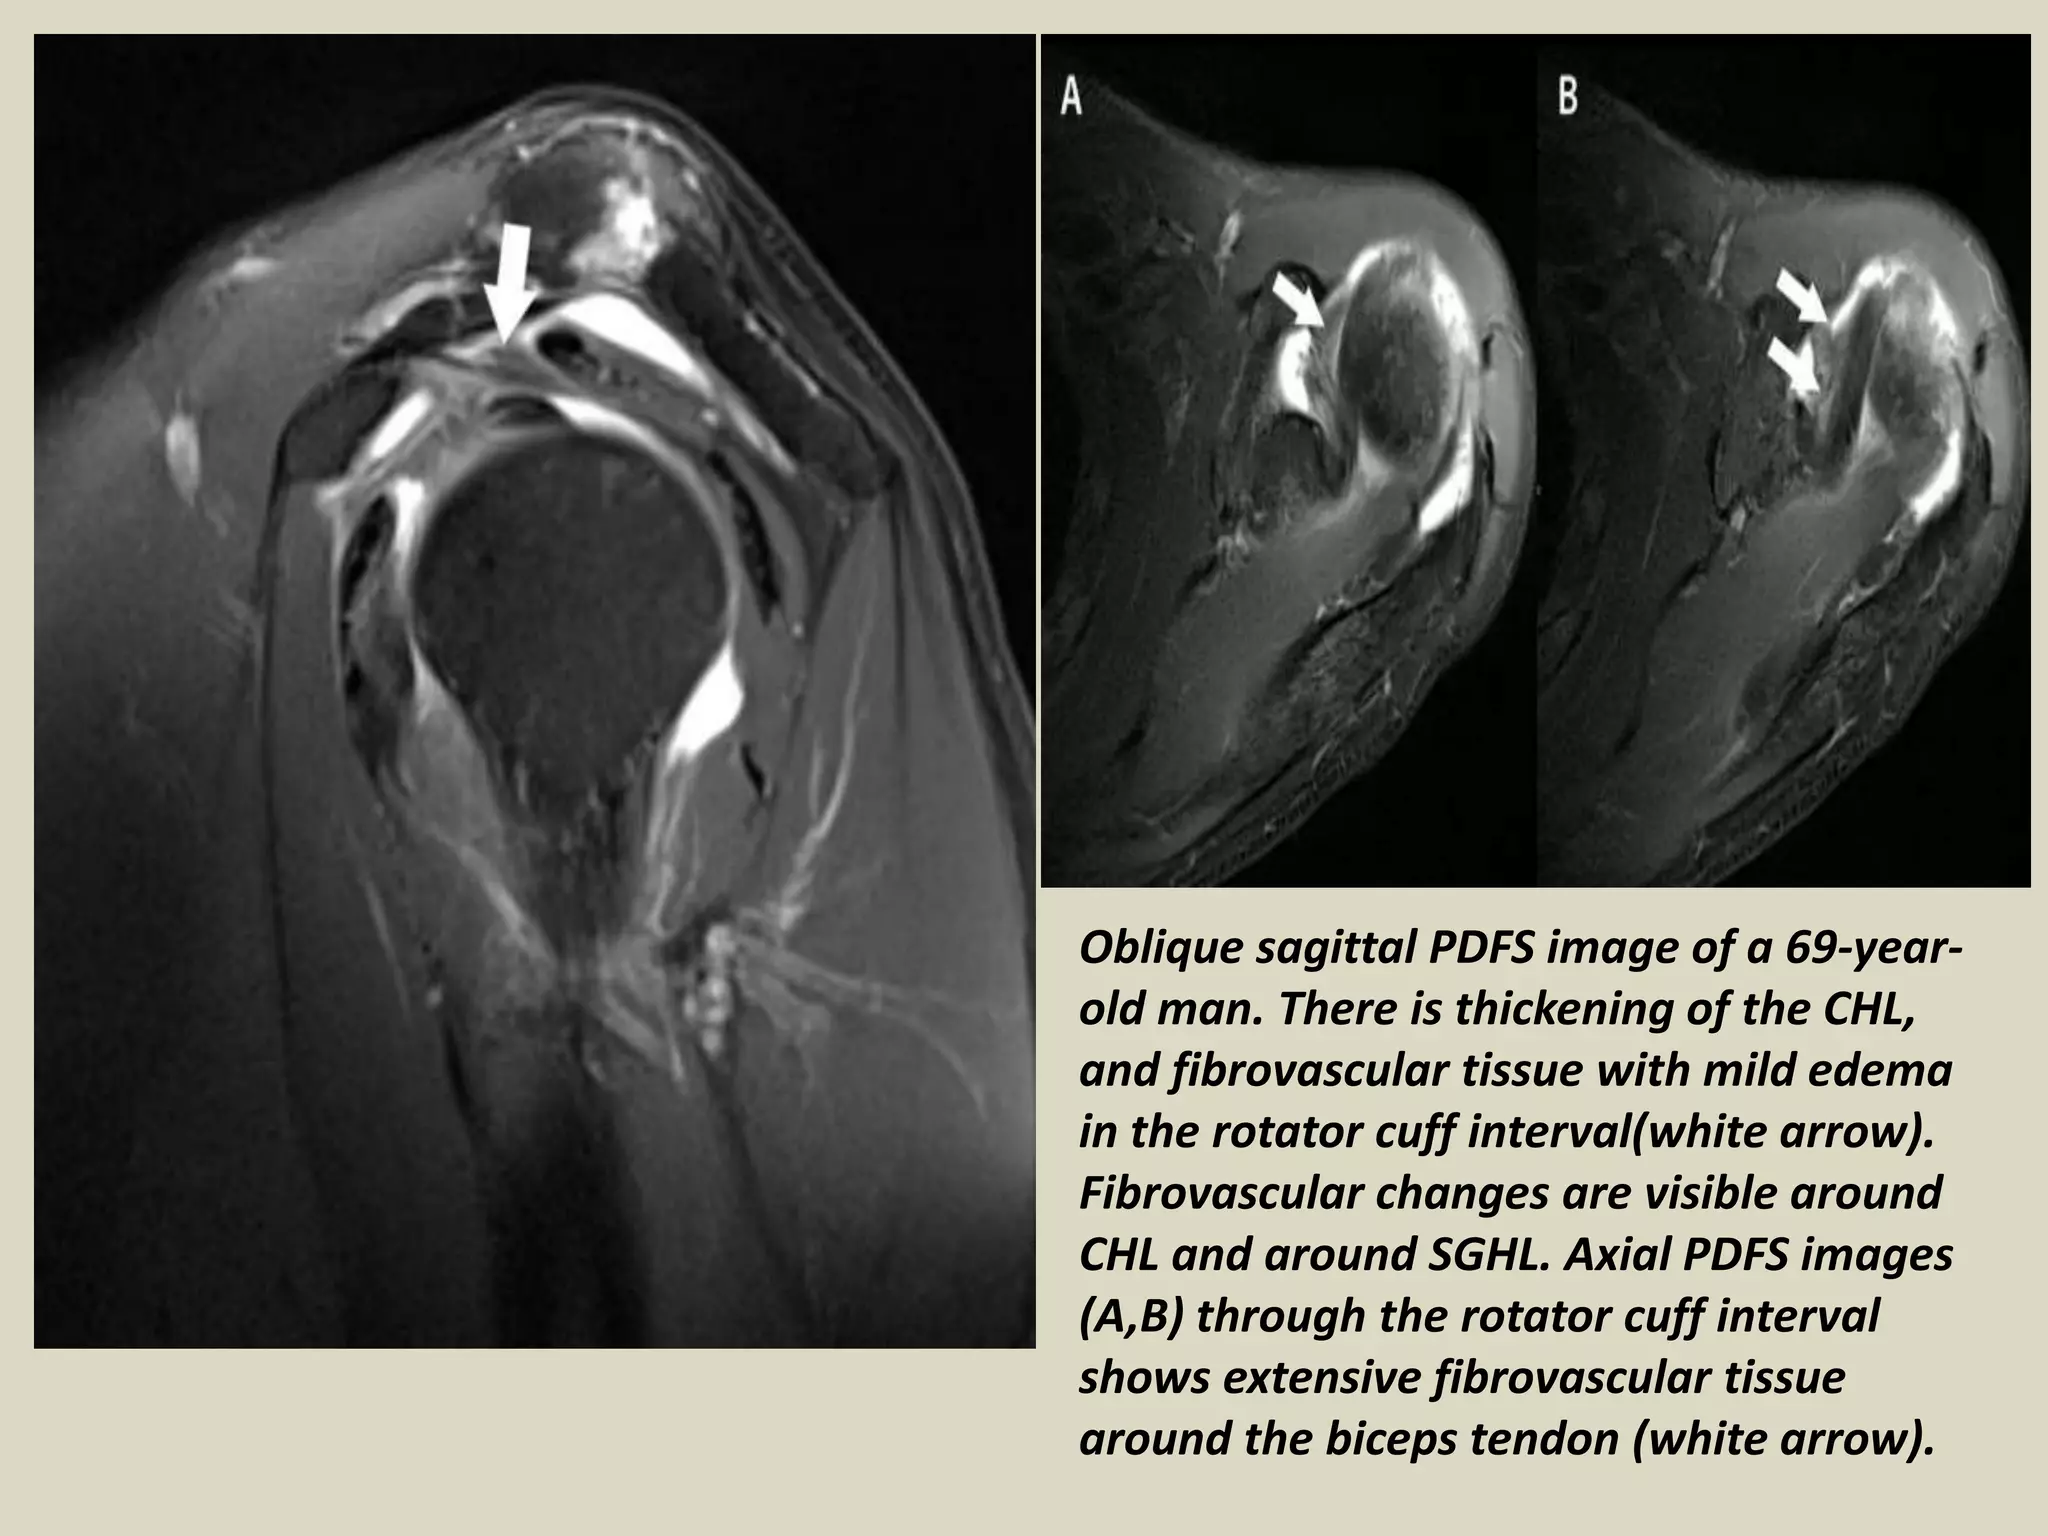

MRI Appearance of Adhesive Capsulitis Illinois Chiropractic Society Adhesive Capsulitis Hip Mri The clinical suspicion of idiopathic adhesive capsulitis of the hip (iach) involves restricted range of motion and normal hip. The diagnosis is confirmed by arthroscopy. There remains a paucity of literature addressing adhesive capsulitis of the hip (ach), making the diagnosis and treatment a. Adhesive capsulitis of the hip (ach) is a rare clinical entity. Magnetic resonance imaging (mri) can. Adhesive Capsulitis Hip Mri.

MRI Appearance of Adhesive Capsulitis Illinois Chiropractic Society Adhesive Capsulitis Hip Mri There remains a paucity of literature addressing adhesive capsulitis of the hip (ach), making the diagnosis and treatment a. Inflammatory conditions, including adhesive capsulitis of the hip, crystal deposition disease, polymyalgia rheumatica, and. In mri, there is thickening of the joint capsule with edema and pericapsular enhancement. Magnetic resonance imaging (mri) can be helpful. Similar to adhesive capsulitis of the. Adhesive Capsulitis Hip Mri.

Adhesive Capsulitis MRI Sumer's Radiology Blog Adhesive Capsulitis Hip Mri The diagnosis is confirmed by arthroscopy. The clinical suspicion of idiopathic adhesive capsulitis of the hip (iach) involves restricted range of motion and normal hip. There remains a paucity of literature addressing adhesive capsulitis of the hip (ach), making the diagnosis and treatment a. Inflammatory conditions, including adhesive capsulitis of the hip, crystal deposition disease, polymyalgia rheumatica, and. Magnetic resonance. Adhesive Capsulitis Hip Mri.

Adhesive capsulitisMRI Sumer's Radiology Blog Adhesive Capsulitis Hip Mri Reported capsular thickening in patients diagnosed with adhesive. There remains a paucity of literature addressing adhesive capsulitis of the hip (ach), making the diagnosis and treatment a. Inflammatory conditions, including adhesive capsulitis of the hip, crystal deposition disease, polymyalgia rheumatica, and. Adhesive capsulitis of the hip (ach) is a rare clinical entity. Similar to adhesive capsulitis of the shoulder, ach. Adhesive Capsulitis Hip Mri.

Adhesive capsulitisMRI Sumer's Radiology Blog Adhesive Capsulitis Hip Mri Similar to adhesive capsulitis of the shoulder, ach is characterized by a painful. Magnetic resonance imaging (mri) can be helpful. The clinical suspicion of idiopathic adhesive capsulitis of the hip (iach) involves restricted range of motion and normal hip. There remains a paucity of literature addressing adhesive capsulitis of the hip (ach), making the diagnosis and treatment a. Reported capsular. Adhesive Capsulitis Hip Mri.